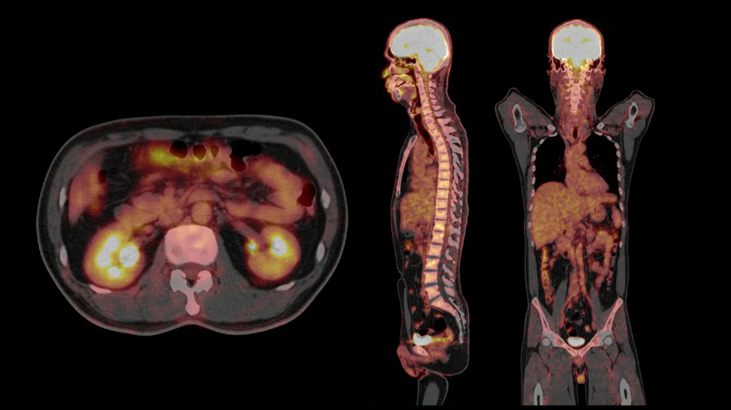

Servicio de PET/CT de Alta Precisión con Siemens Biograph Trinion

Última tecnología para un diagnóstico más preciso.

Imágenes moleculares que permiten un diagnóstico avanzado en:

ONCOLOGÍA

La Tomografía por Emisión de Positrones (PET) combinada con la Tomografía

Computarizada (CT) es la técnica más avanzada para evaluar la actividad metabólica y la anatomía de órganos y tejidos en una sola exploración.

Permite detectar enfermedades en fases tempranas, monitorizar tratamientos y planificar intervenciones de manera segura y precisa.

Nuestro equipo: Siemens Biograph Trinion

En la Clínica de Marly contamos con el Siemens Biograph Trinion, un equipo de última generación que se destaca por:

El Biograph Trinion representa uno de los estándares tecnológicos más avanzados en diagnóstico PET/CT a nivel mundial, respaldado por la innovación y experiencia de Siemens Healthineers.